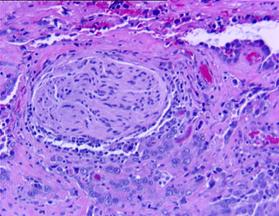

Fig.3 Carcinom in situ (HEx10) [51].